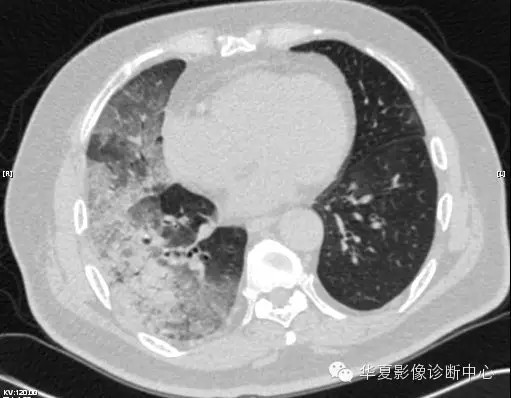

【病例学习】甲型H7N9禽流感一例

男性 63

发热咳嗽5天

2013-4-5拍片示右肺实变,收入院,追问病史,发病期间肌肉酸痛,头痛,无腹痛腹泻,无明显胸闷气急,无意识改变。有高血压病史,无其它病史。

2013-4-7CT进一步检查。

最终诊断:H7N9。